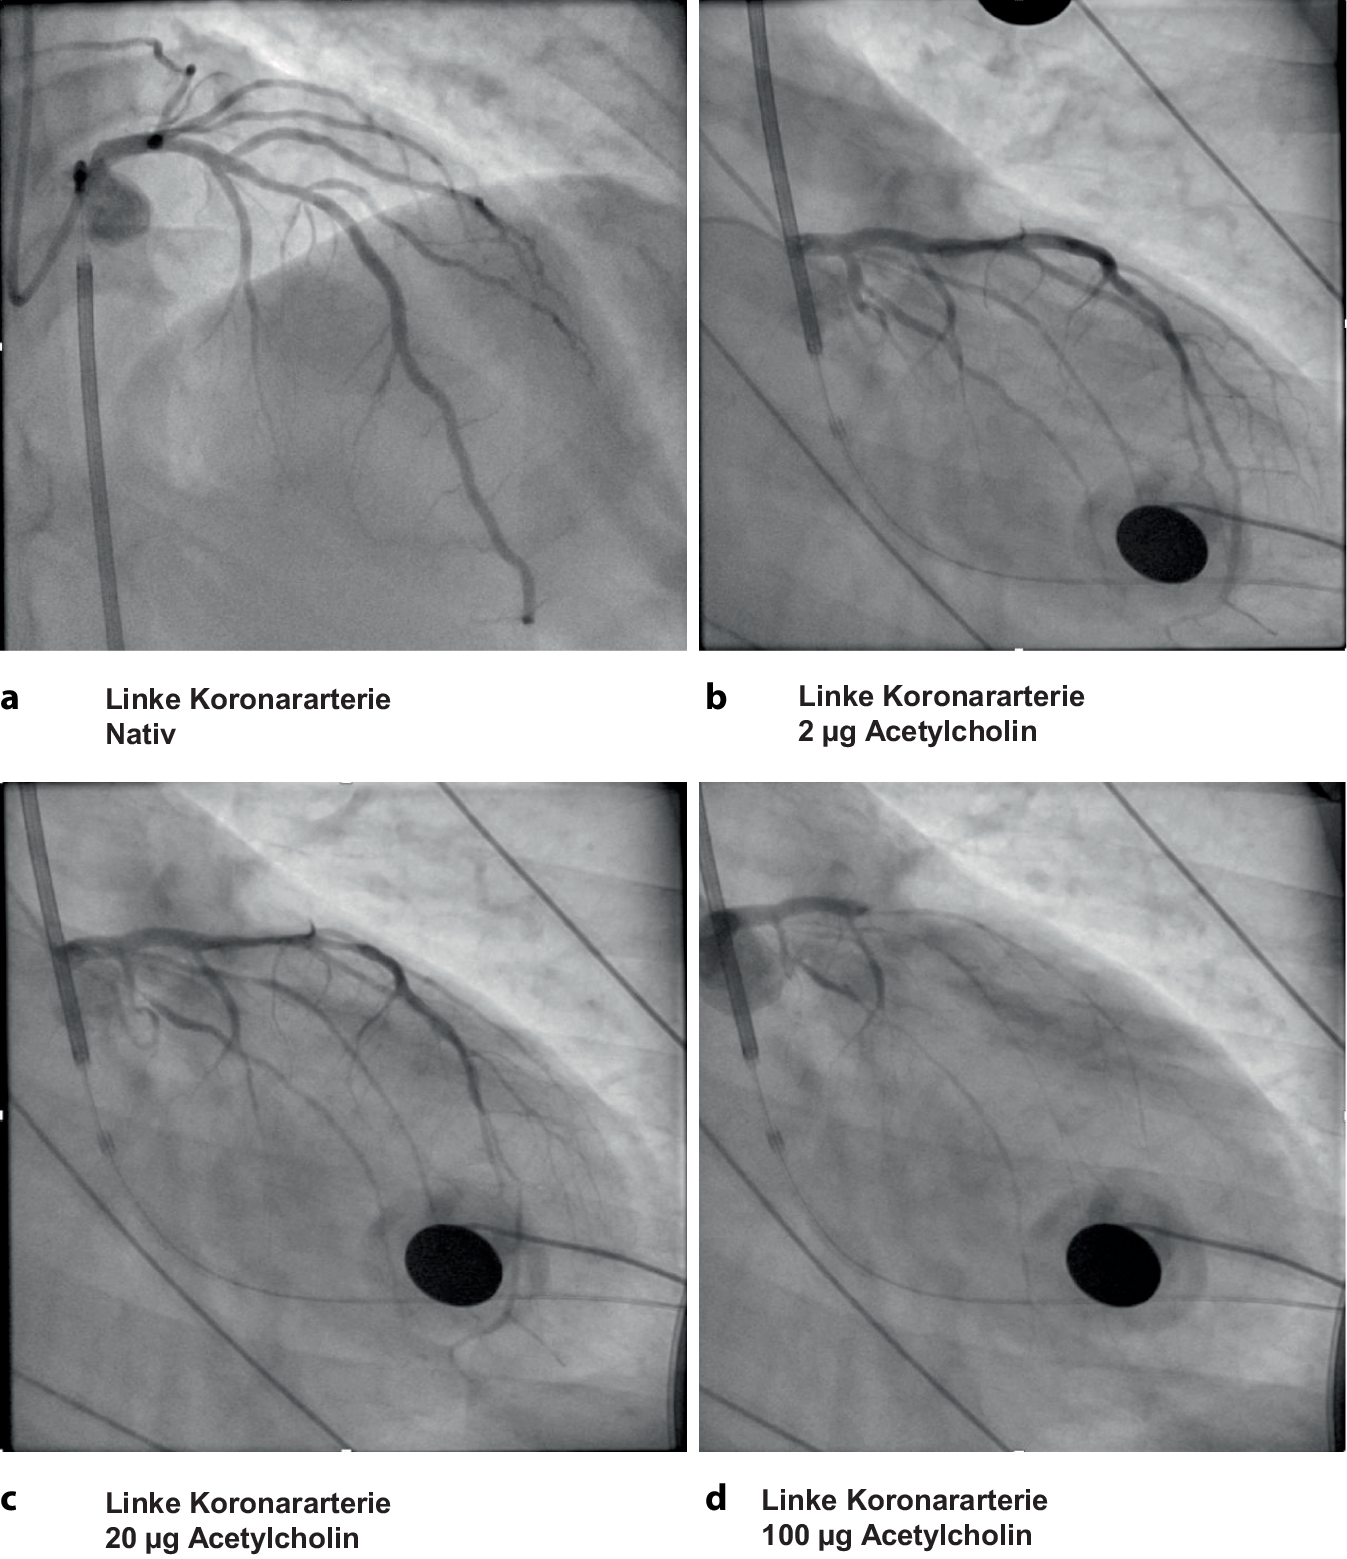

Zur weiteren Abklärung dieser Arbeitsdiagnose wurde eine funktionelle Koronararteriendiagnostik mit Acetylcholintestung indiziert [1, 3]. Die Koronarangiographie schloss erneut relevante Koronarstenosen unter Nativbedingungen aus (Abb. 3a). Es erfolgte dann die schrittweise intrakoronare Applikation von Acetylcholinboli (2 µg, 20 µg, 100 µg). Hierunter entwickelte der Patient Thoraxschmerz, der vergleichbar war zu den vorherigen Episoden. Dosisabhängig kam es dann zu dynamischen ST-Strecken- und T‑Wellen-Veränderungen, die von einem progressiven epikardialen Vasospasmus der Vorderwandarterie begleitet wurden (Abb. 3b, c). Letztlich resultierte die Applikation von 100 µg Acetylcholin in einer Verschmälerung der Vorderwandarterie > 90 % des Ausgangsdiameters, es kam fast zur Totalokklusion (Abb. 3d). Nach zügiger intrakoronarer Applikation von Glyceroltrinitrat konnte der Vasospasmus aufgehoben werden, hierunter nahm dann auch der Thoraxschmerz umgehend ab. Der so provozierte Vasospasmus war mit diesem Befund nach Acetylcholintestung deutlich von einer endothelialen Dysfunktion abzugrenzen und in Einklang zu bringen mit der Diagnose einer vasospastischen Angina pectoris [2].

Koronarangiographie und Acetylcholintestung. a Native Darstellung der linken Koronararterie. b Darstellung der linken Koronararterie nach intrakoronarer Applikation von 2 µg Acetylcholin. Es zeigt sich eine diskrete Gefäßverschmälerung im mittleren Segment. c Darstellung der linken Koronararterie nach intrakoronarer Applikation von 20 µg Acetylcholin. Es zeigt sich eine fortgeschrittene Gefäßverschmälerung betont im mittleren Segment. d Darstellung der linken Koronararterie nach intrakoronarer Applikation von 100 µg Acetylcholin. Es zeigt sich nahezu eine Totalokklusion